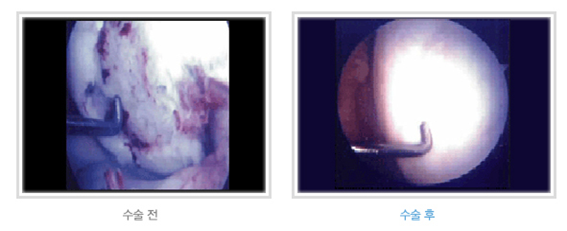

연골판 이식술